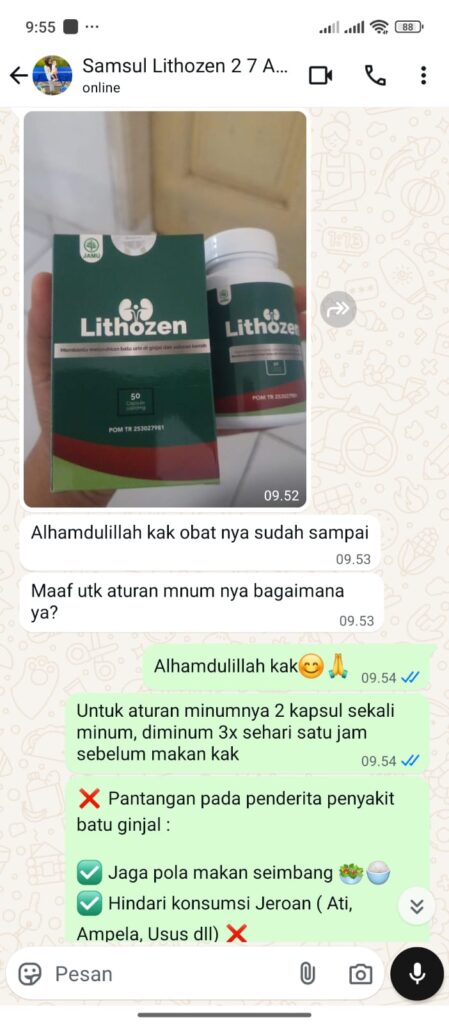

Ini Kata Mereka Yang Sudah Berhasil Sembuh dari Gangguan Ginjal

Makanan Apa Yang Tidak Boleh Dimakan Oleh Penderita Gangguan Ginjal?

Penderita gangguan ginjal sebaiknya menghindari makanan tinggi garam, protein hewani berlebihan, dan makanan tinggi oksalat seperti bayam, cokelat, dan kacang-kacangan. Hindari juga minuman bersoda, makanan olahan, serta alkohol karena bisa memperparah kondisi ginjal dan memicu pembentukan batu baru.